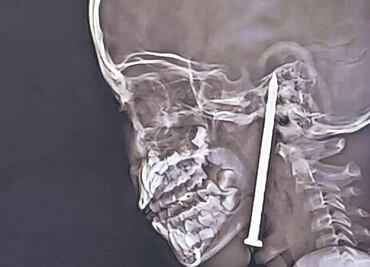

• ¿Fue un MILAGRO? La increíble historia de una niña que SOBREVIVIÓ a un CLAVO en el CRÁNEO

¿Fue un MILAGRO? La increíble historia de una niña que SOBREVIVIÓ a un CLAVO en el CRÁNEO

Aunque sus familiares sabían desde el inicio que la situación era grave, desconocían la magnitud del daño